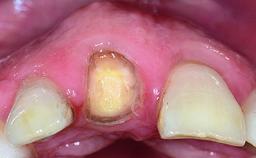

A healthy 23-year-old female patient was referred for a consultation on replacing tooth 21 with an implant-supported restoration. The patient had recently moved to the area and reported a history of endodontic and periodontal treatment for tooth 21. The tooth had been deemed non-restorable by her previous periodontist but since she was going to be moving, he recommended consulting to a dentist in her new city to continue her treatment. A review of her medical history yielded no significant findings and no known drug allergies. The analysis of her smile revealed a medium to high symmetrical smile line and a slightly discolored tooth 21.

Replacement of a Failing Upper Left Central Incisor: Immediate Placement of an RC Bone Level Implant and Provisionalization